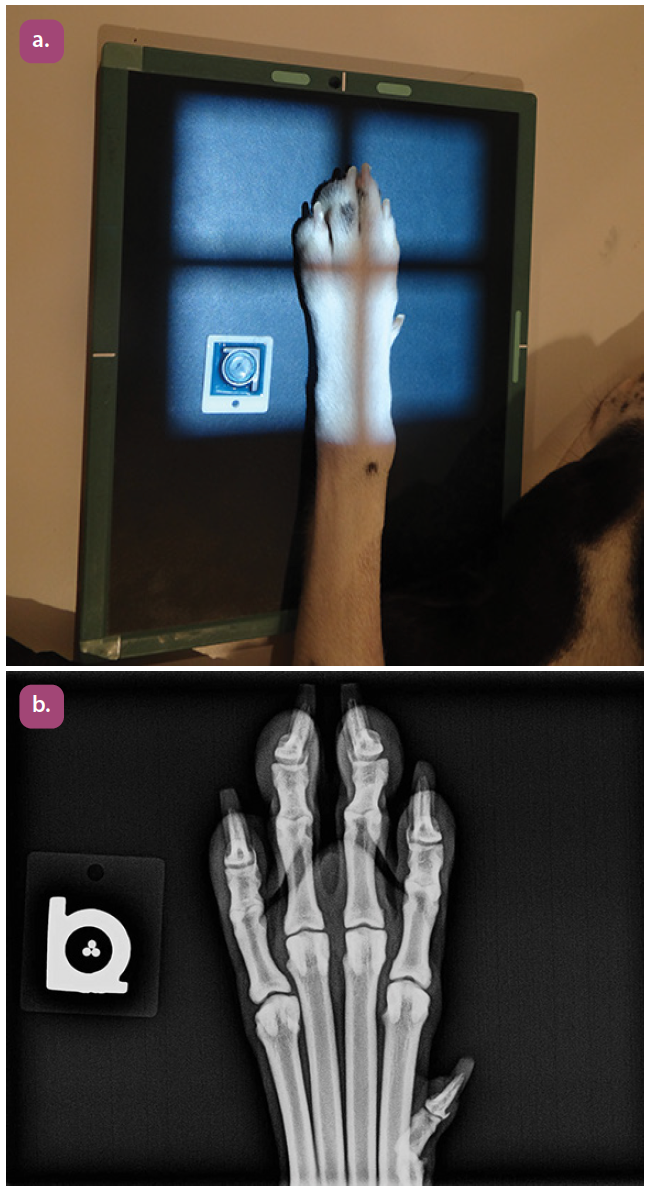

dorsopalmar projection of the digits

lateral projection of the digits